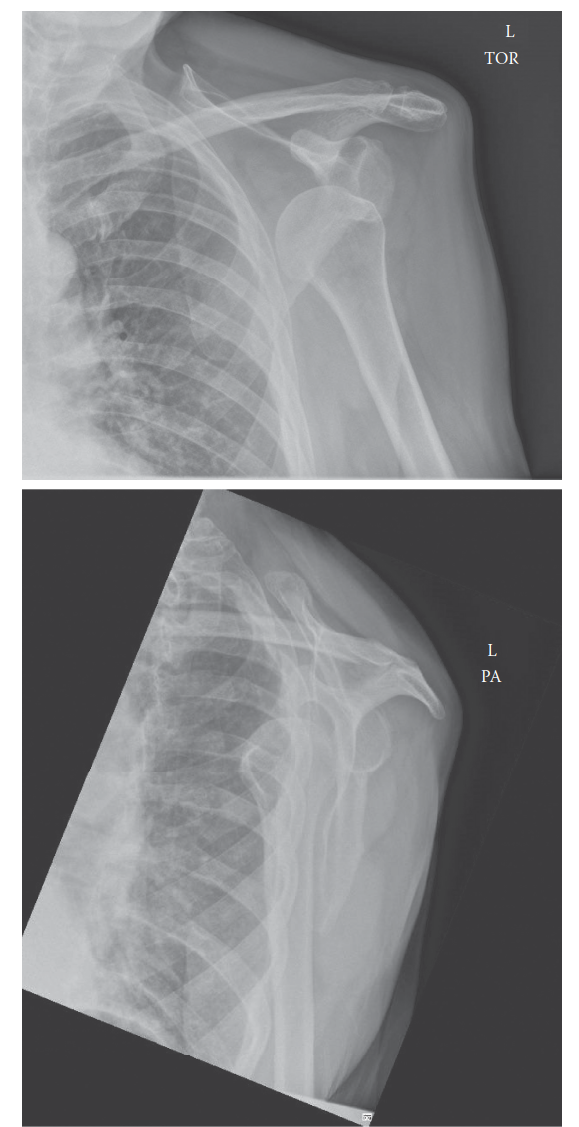

Management of Proximal Humerus Fracture 1. Describe these radiographs. Show Answer Show Explanation 2. How wo…

A 45-year-old man with epilepsy is brought to the emergency department following a sei- zure. He complains of…